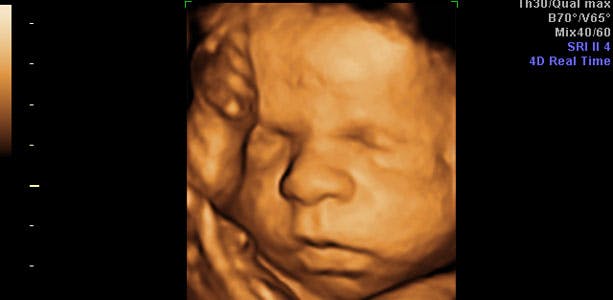

Gravid uge 31: Kraftig vækst

Testiklerne hos drengene begynder at vandre ned mod deres endestation - pungen. Hos 97 procent kan stenene mærkes i pungen efter fødslen. Jordemoderen undersøger altid dette ved børneundersøgelsen. Såfremt testiklerne ikke er i pungen og ikke kommer det spontant senere, kan de hjælpes på plads med en mindre operation. I slutningen af ugen måler barnet cirka 38 cm og vejer omkring 1700 gram. Lårbenet måler cirka 5,8 centimeter, maveomkredsen cirka 27,5 centimeter og hovedet 7,9 centimeter i diameter.